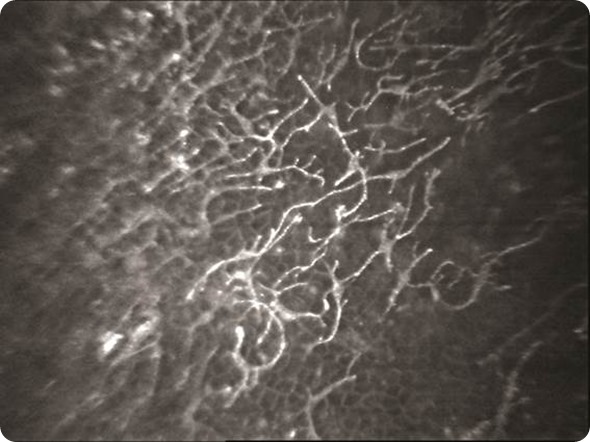

Dendritic cells in the cornea imaged by confocal microscopy.

During the early years, he worked mainly in the areas of contact lenses and infection and published seminal work on identifying infections with the confocal microscope. Later he spent time understanding and treating corneal diseases in children till he found his calling in lamellar corneal surgery, corneal transplantation, keratoconus and refractive surgery.